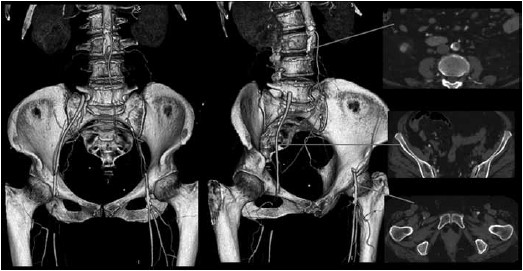

A paciente da questão anterior é submetida a uma angiotomografia de Aorta e ilíacas, sendo a reconstrução arterial 3D e cortes axiais selecionados apresentados a seguir.

Diante do quadro clínico e achado do exame de imagem, assinale a alternativa que corresponde respectivamente à principal hipótese diagnóstica e à conduta terapêutica.